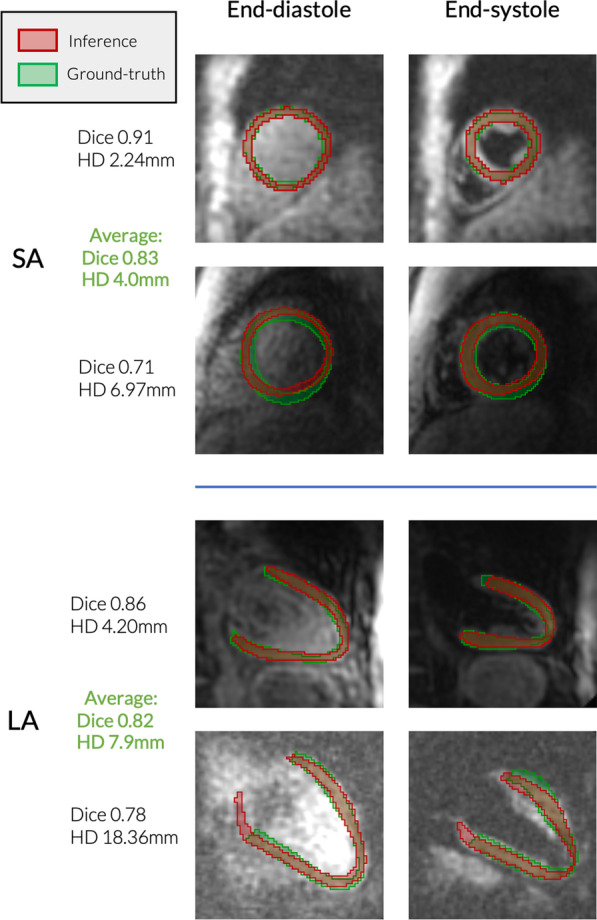

Segmentation results

2D + time DynU-Net segmentation inference on an independent test-set of 83 short-axis and 25 long-axis slices achieved a DICE score of 0.83 ± 0.05 and a Hausdorff distance of 4.0 ± 1.1 mm for the short-axis and 0.82 ± 0.03 and 7.9 ± 3.9 mm respectively for the long axis. This led to a similar segmentation performance to the original nnU-Net implementation, with no statistical difference for LAx models (p for Dice and Hausdorff distance on the overall test set) and a minor difference for SAx models (p ). Additional precision and sensitivity measures can be found in Table 5. Figure 4 shows segmentation results from both LAx andSAx test sets. The training time was reduced by a factor 4 compared to the nnU-Net framework, reducing this time from 83 to 21 h for fourfold CV training on the SAx dataset, and respectively from 51.5 h to 13 h for LAx. GPU inference was achieved in under 1 s for every case, compared to up to 30 min required to define contours with manual segmentation.

Fig. 4.

Segmentation inference examples, 2D + time DynU-Net. Examples of short-axis (SAx) and long-axis (LAx) segmentation results on cases from an independent test set. For each case, the bottom row contains inference examples of worst performance at end-diastole (left column) and end-systole (right column), while the top row contains inference examples with top performance, more typical